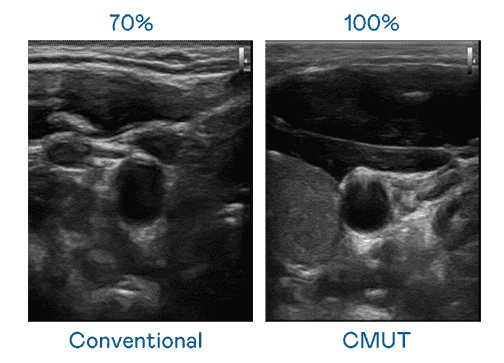

CMUT 技术是一种用电容式微机电元件来产生超音波讯号的技术。。。。与传统 PZT 压电式技术相比,,,,CMUT 频宽增加 30%,,,,更宽频的超音波讯号让影像解析度大幅提升,,,,是实现高影像品质医疗超音波扫描、、促进精准医疗发展的关键技术。。。

大频宽带来超清晰影像

超音波影像的解析度高低,,,,首先取决于探头能发出的讯号频宽。。红龙扑克 CMUT 可提供高清晰的超音波讯号,,,,提供高频宽、、高灵敏度、、、、影像纹理细节更高的超音波影像,,,,协助医护人员缩短影像判读时间及利用精准的医疗影像进行诊断。。。。